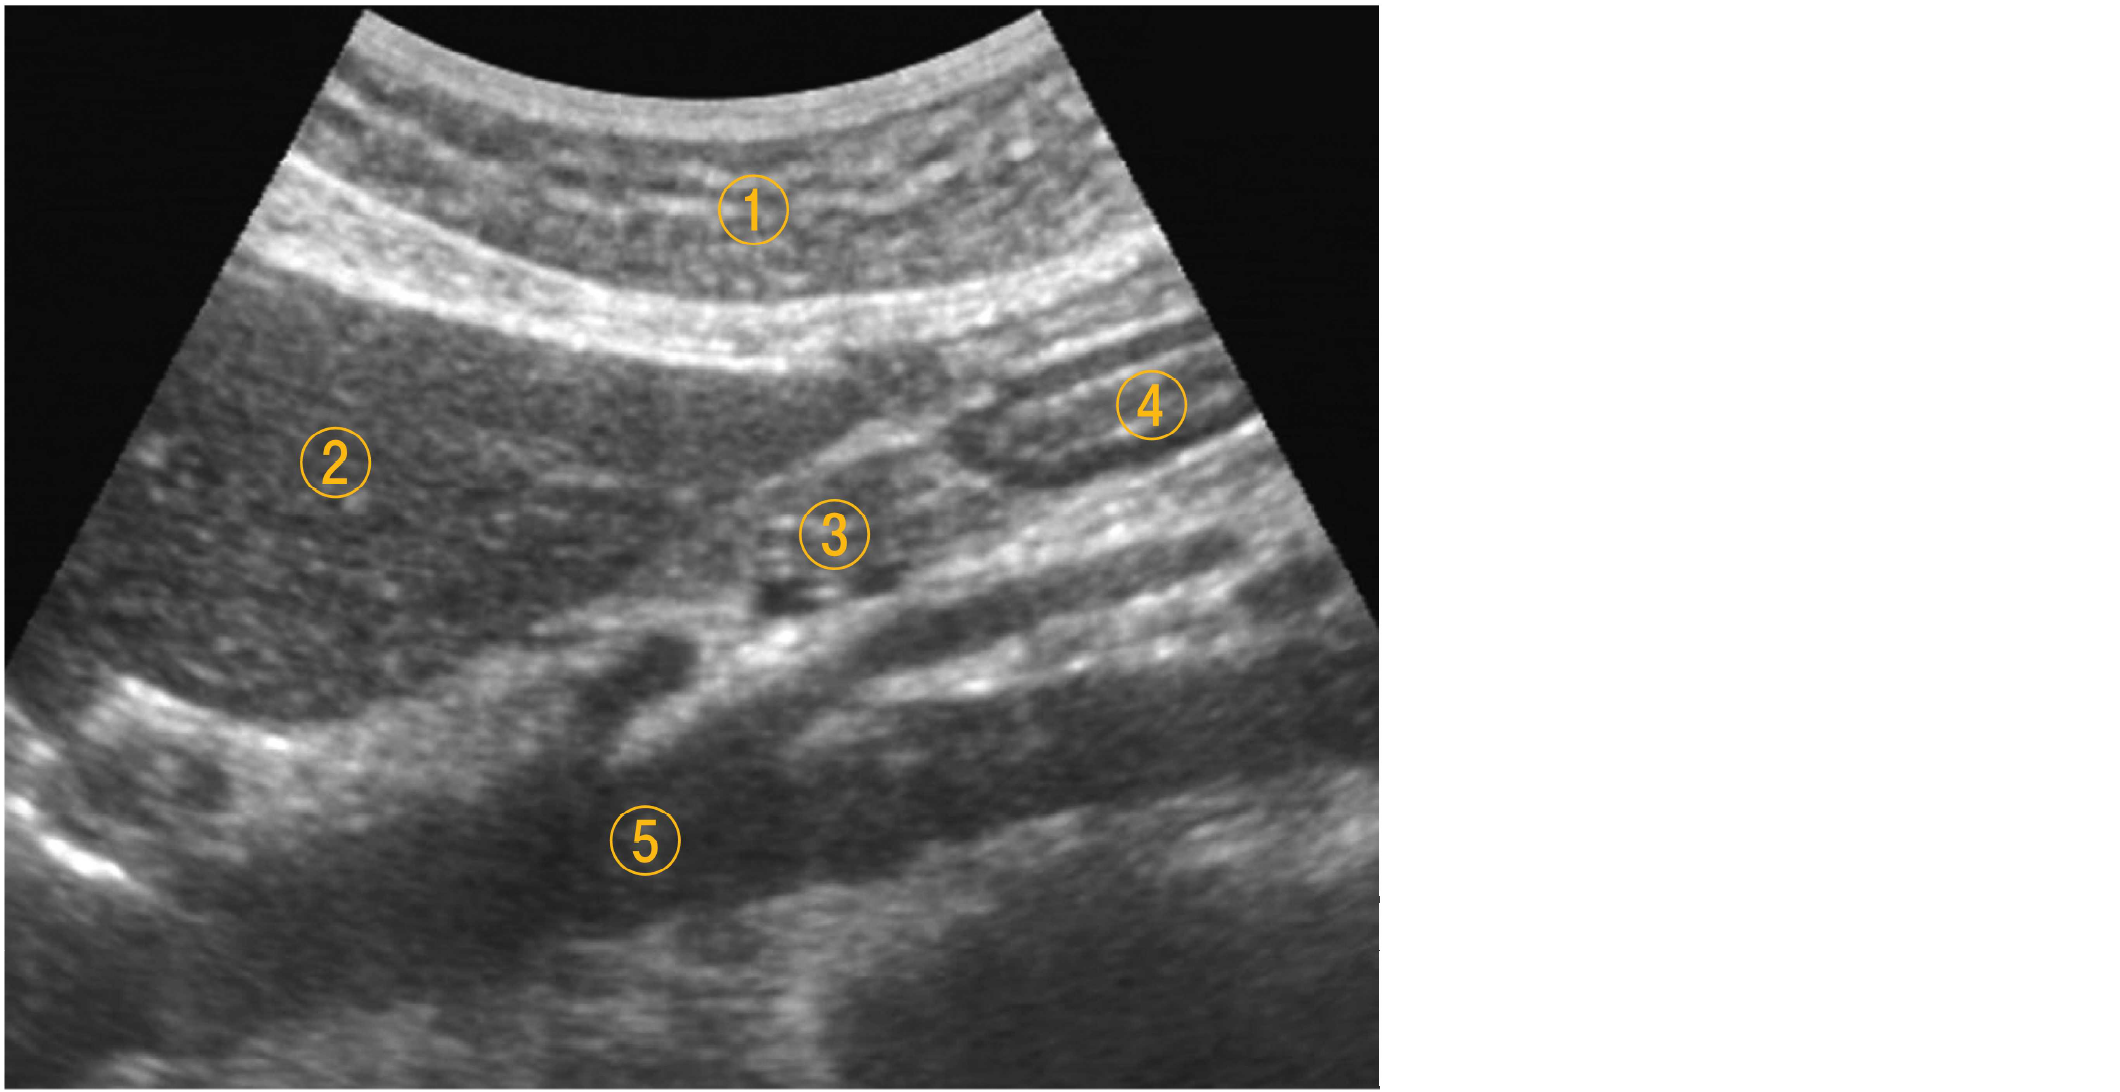

心窩部縦走査による上腹部の超音波像を示す。

番号と臓器・組織の組合せで

誤っている

のはどれか。

1. ①――皮下脂肪

2. ②――肝 臓

3. ③――膵 臓

4. ④――胃

5. ⑤――下大静脈